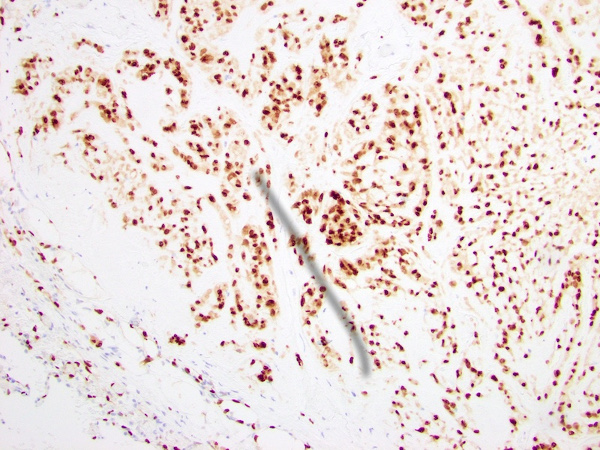

Immunohistochemical stains revealed that the tumor cells were positive for CD31, CD34, and ERG (Figure 3-5). The tumor cells did not mark with pancytokeratin, smooth muscle actin (Figure 6), epithelial membrane antigen, S-100 protein, HMB-45, SOX10, chromogranin, TTF-1 (Figure 7), PAX8, or desmin. No amyloid deposition was identified with Congo red stain.